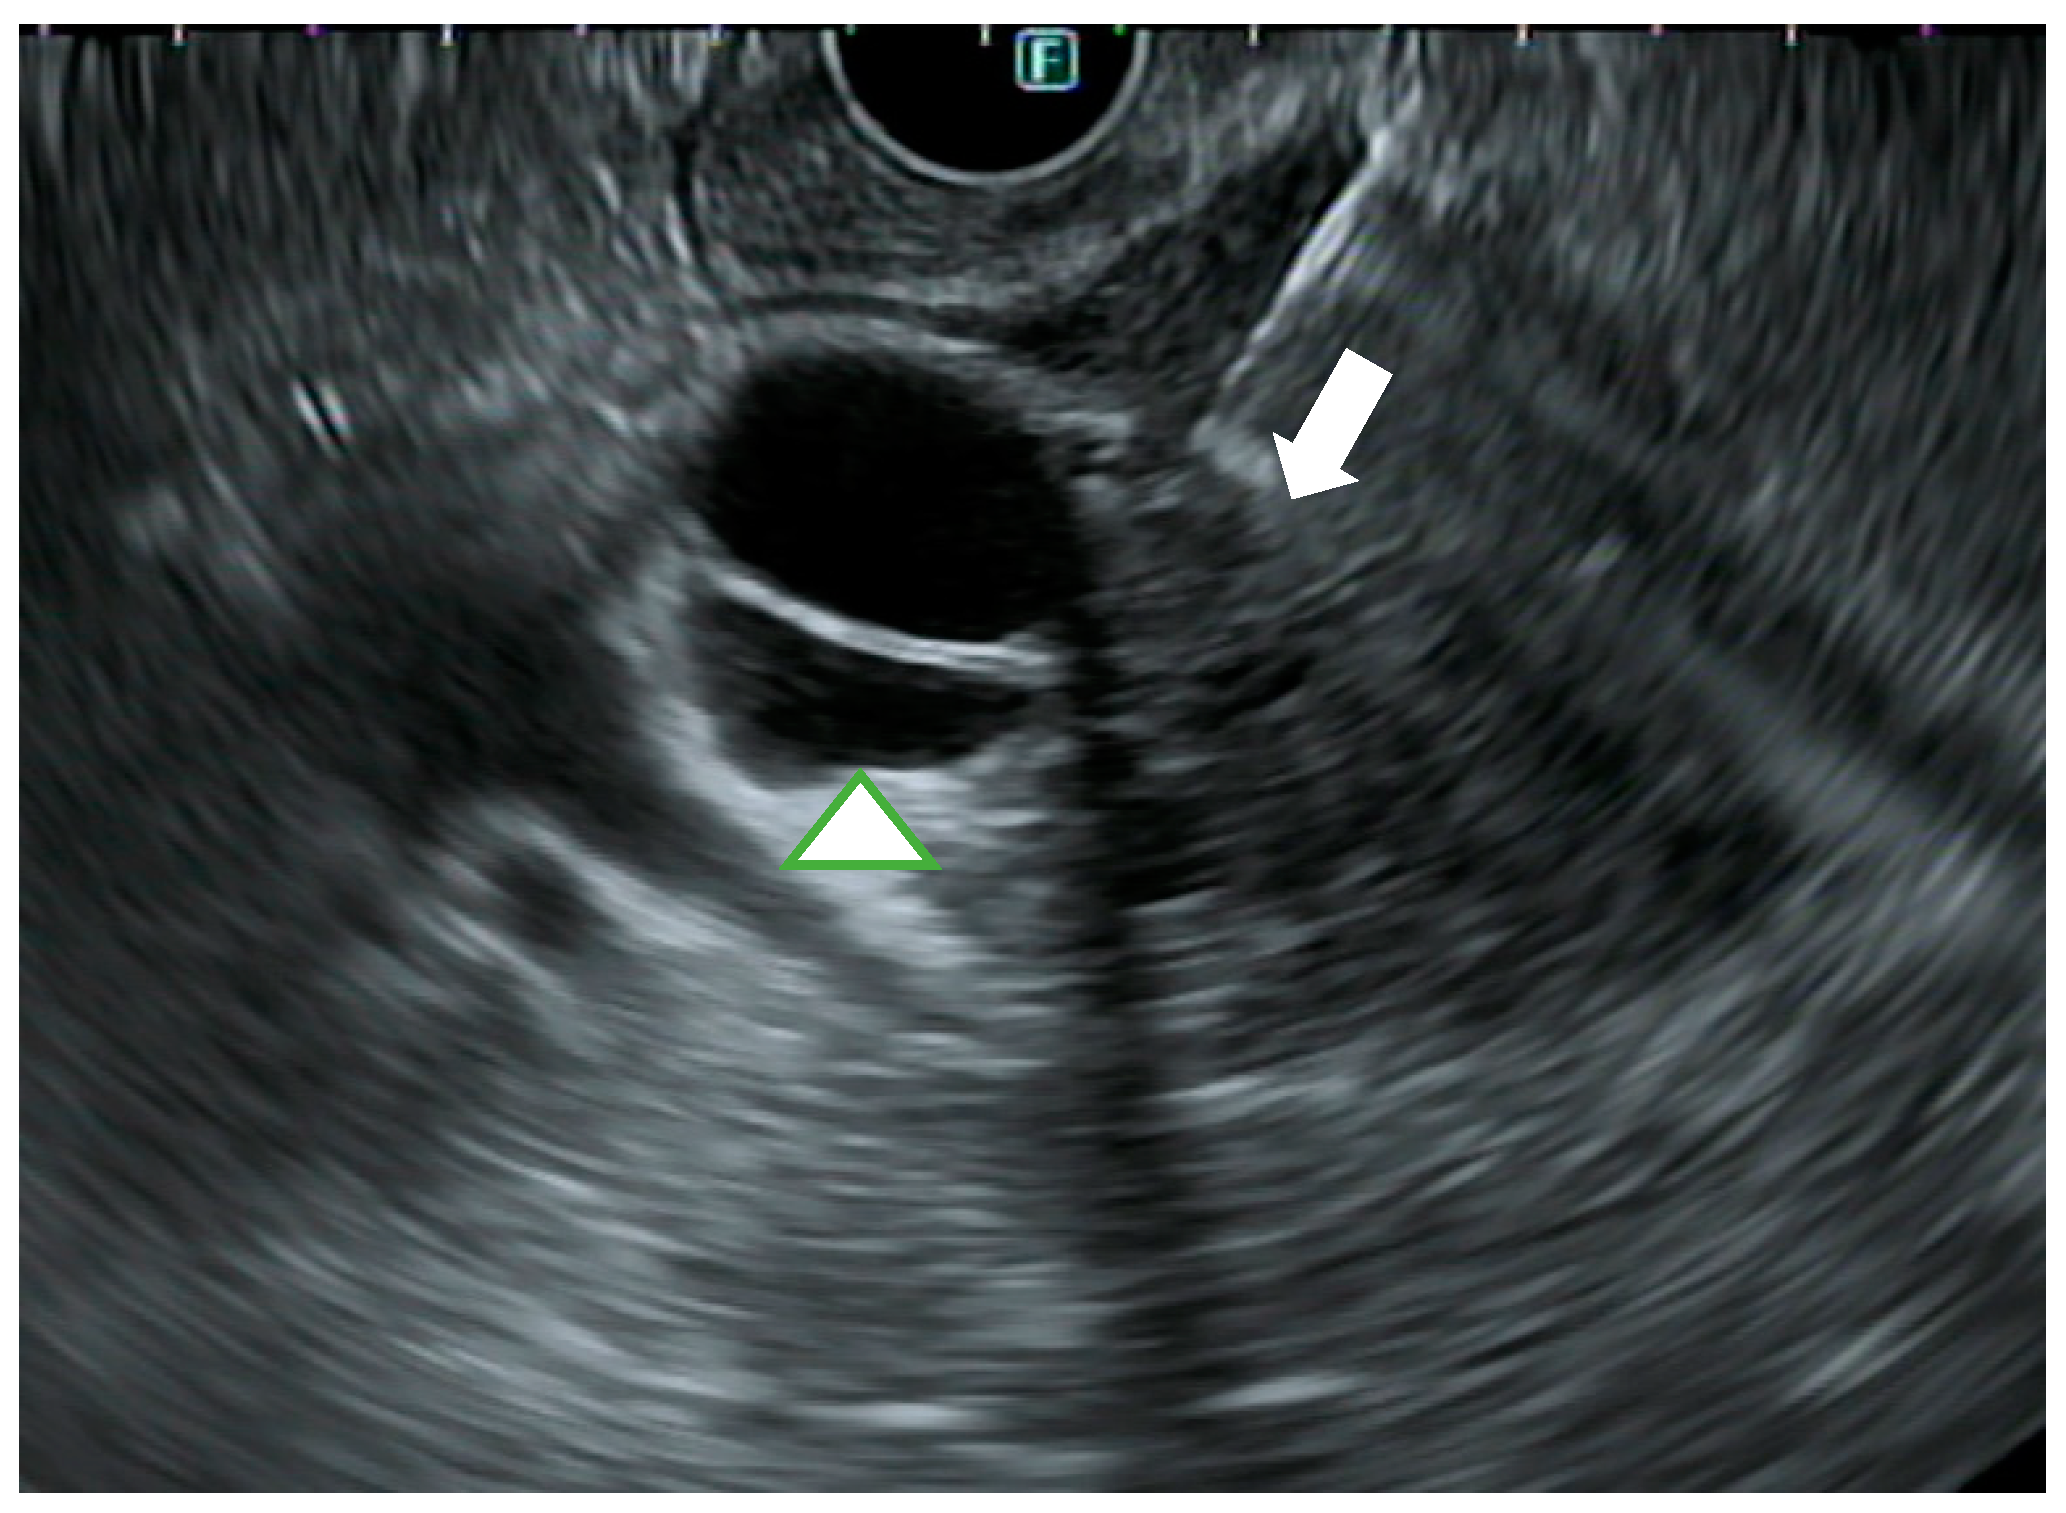

3.2. EUS

4.3. EUS-Guided Biliary Drainage (EUS-BD)